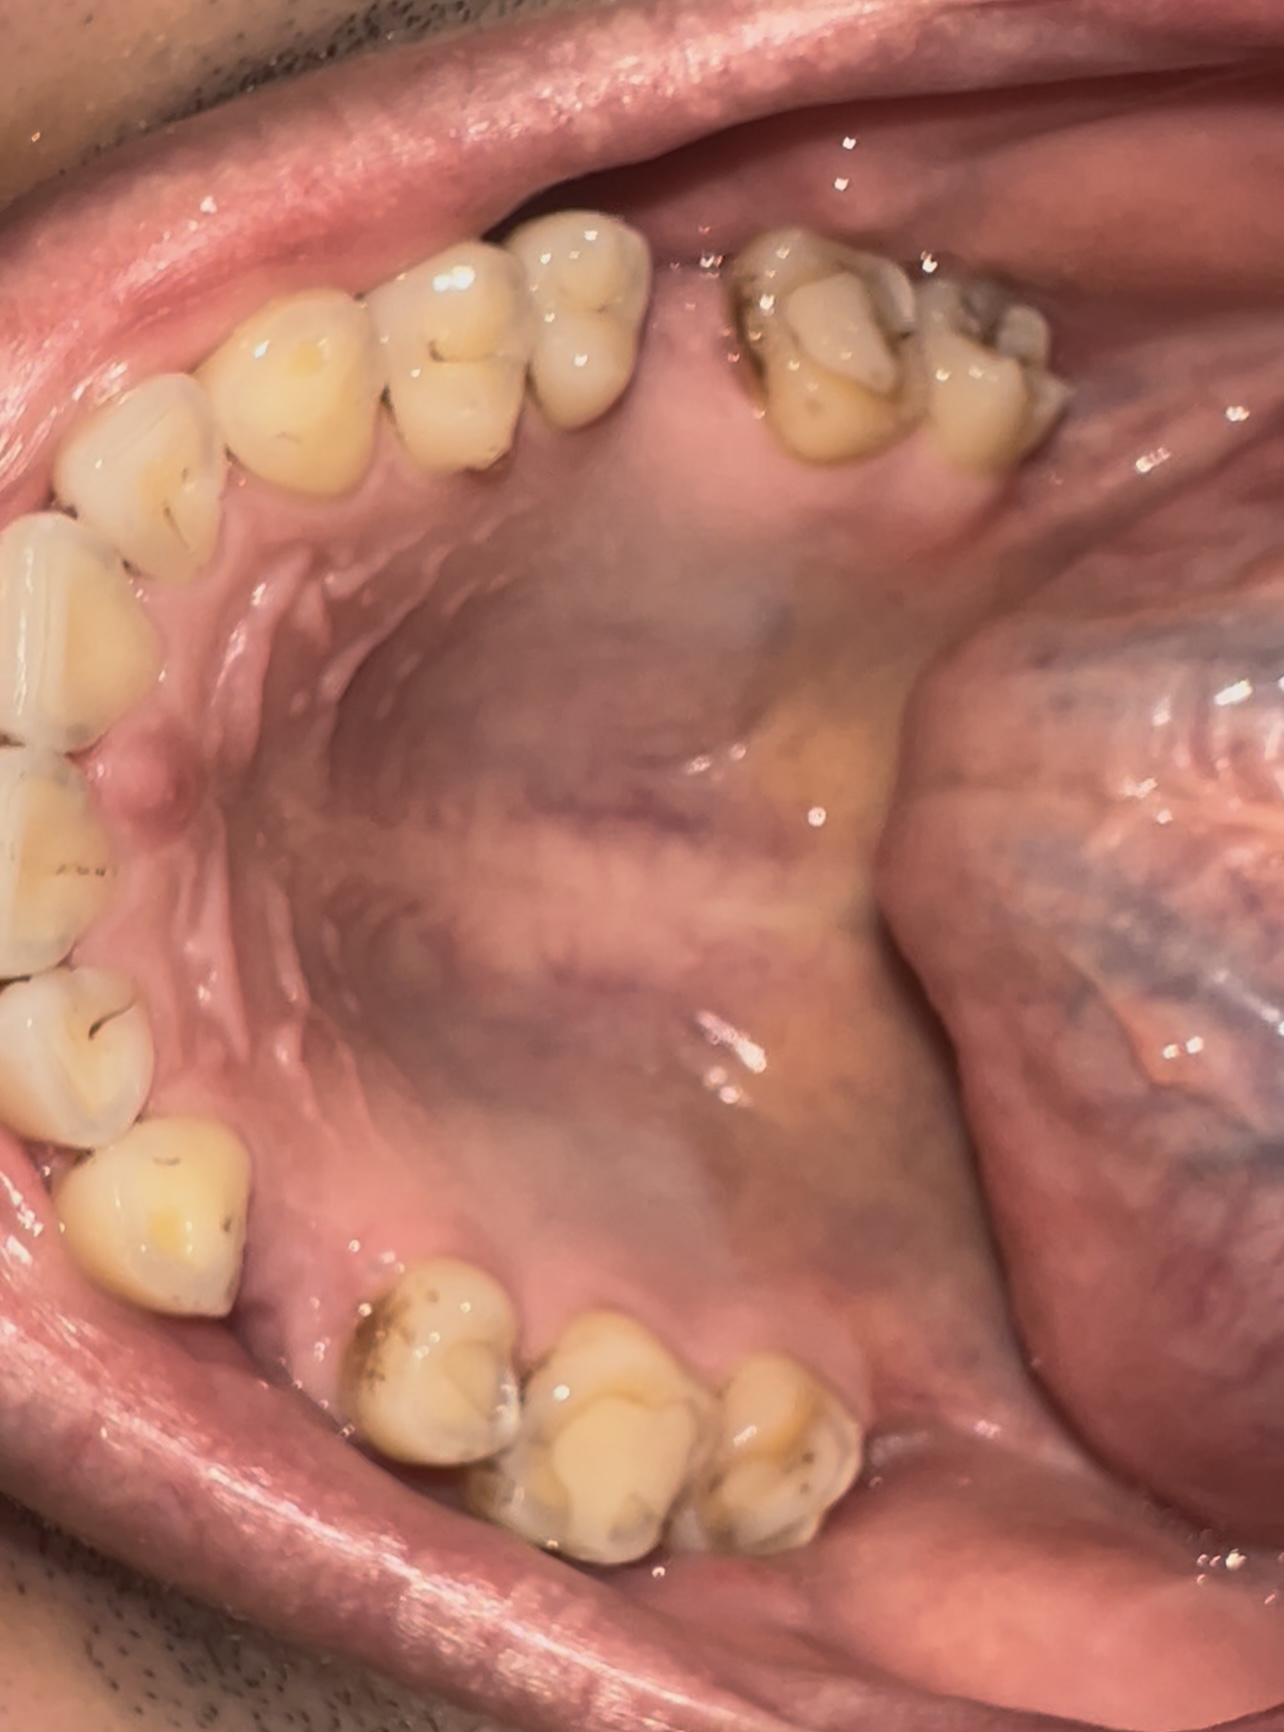

>>1631979 (OP)

Десны, на месте где зубы в них входят такая вот хуйня, отметил рядом если не понятно. Это начало парадонтита или чего-то такого? Камень года 3 не ходил чистить, каюсь. Есть связь с камнем?

Аноним 09/09/25 Втр 12:47:10 1639465 110

Короч пролечил зуб гдет месяц назад, но он болит при накусывании.